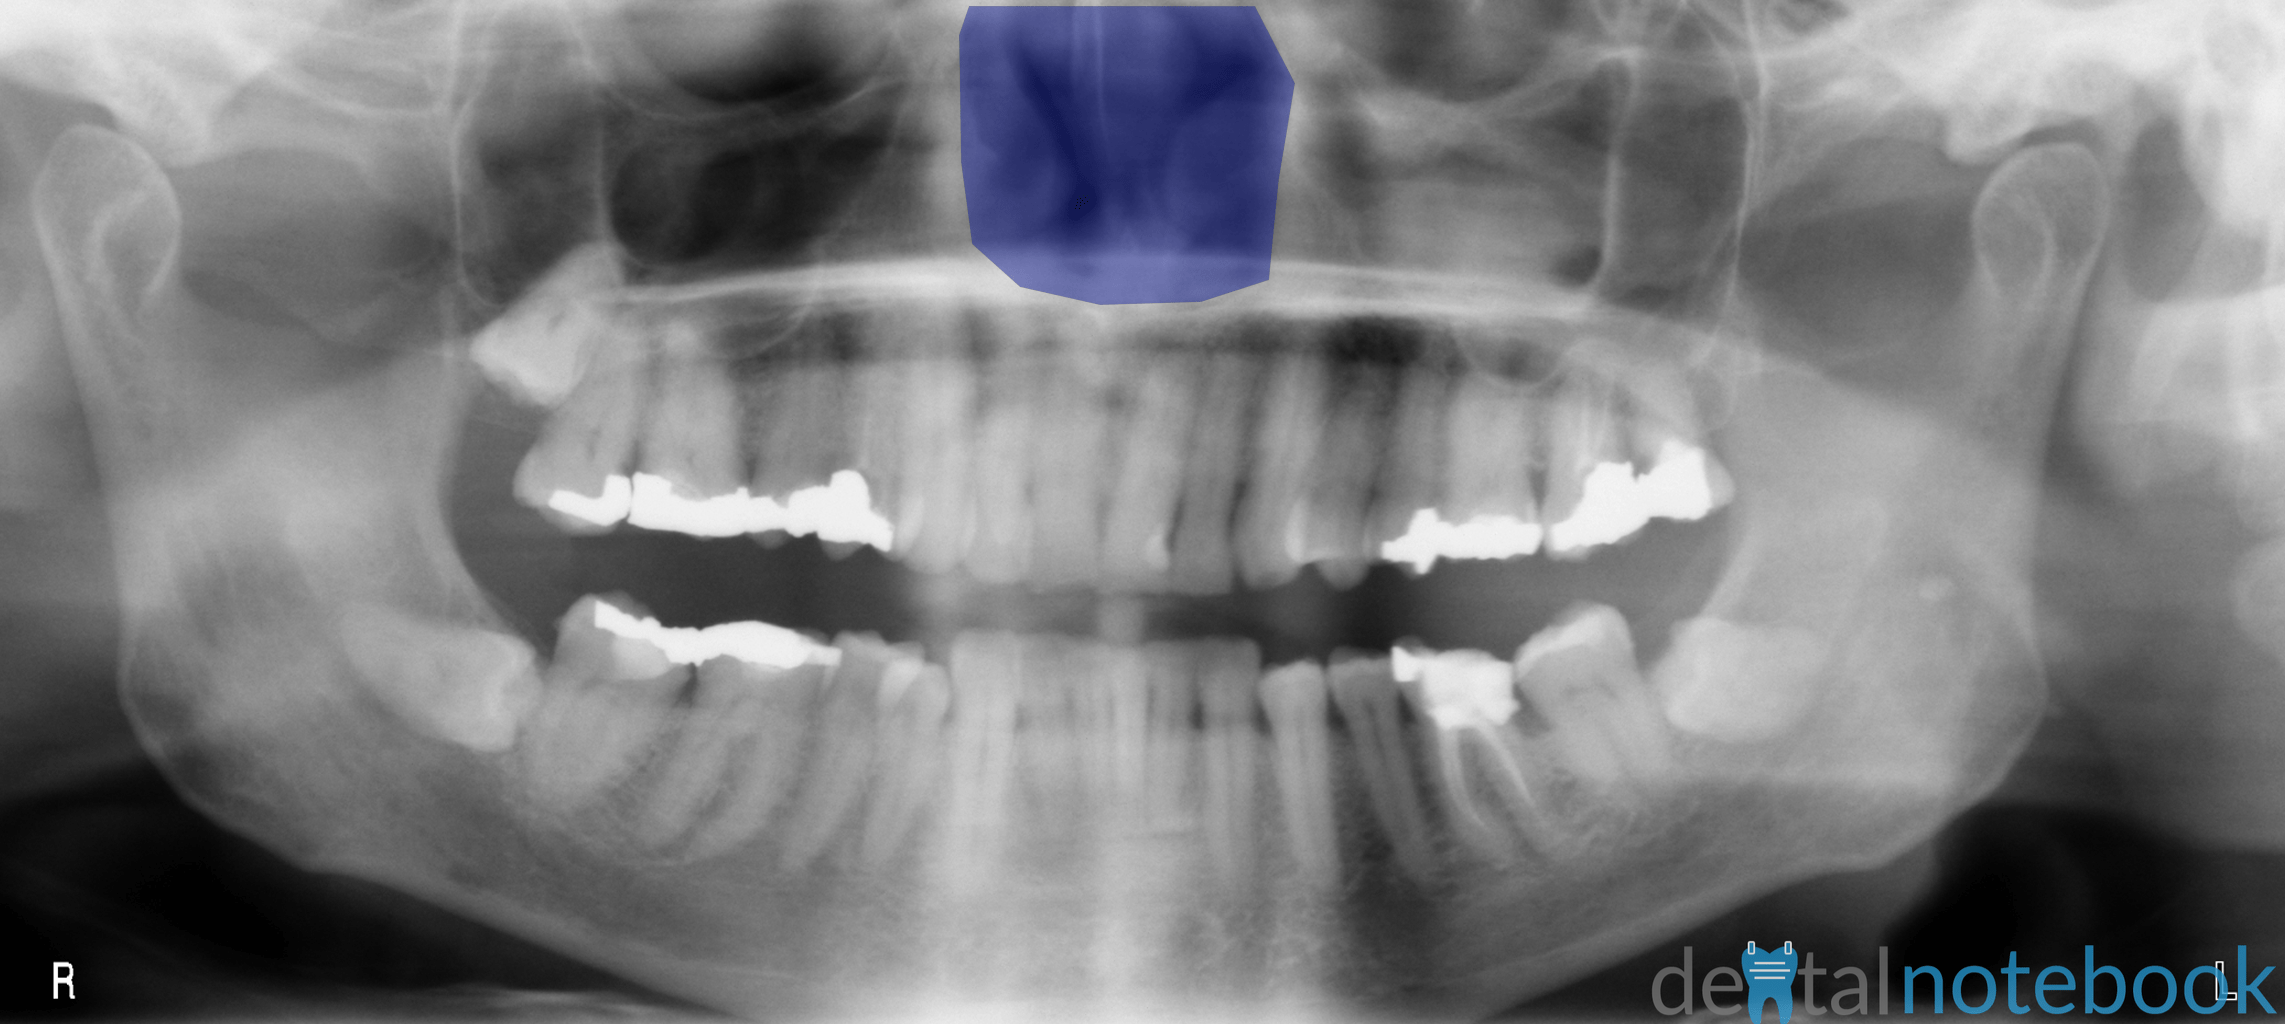

Anatomy of Panoramic Films OPTs/DPTs/OPGs dentalnotebook Panoramic Dental Xray Landmarks A panoramic image displays the patient’s maxillary and mandibular oral and facial structures across a flat surface. Panoramic radiography has become a commonly used imaging modality in dental practice and can be a valuable diagnostic. Panoramic radiography is widely used in dentistry and was considered a significant breakthrough as both jaws, together with the. It is important to understand the. Panoramic Dental Xray Landmarks.

Anatomy of Panoramic Films OPTs/DPTs/OPGs dentalnotebook Panoramic Dental Xray Landmarks Panoramic radiography is widely used in dentistry and was considered a significant breakthrough as both jaws, together with the. For the purposes of this course, we. It is important to understand the landmarks normally seen on panoramic images in order to prevent misdiagnosis of a radiopaque or radiolucent area. Panoramic radiography has become a commonly used imaging modality in dental. Panoramic Dental Xray Landmarks.